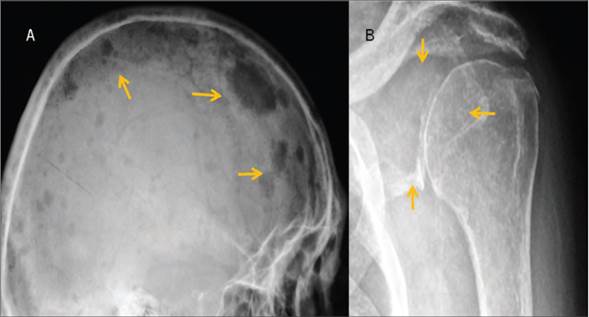

El paciente fue revisado por el servicio de hematología, se valoraron los estudios de laboratorio y RM, por la sospecha de MM y se practicó aspirado de médula ósea que mostró 60% de células plasmáticas anormales (Figura 1), por lo que inició tratamiento médico a base de talidomida más dexametasona, dabigatrán y recibió su primera dosis de ácido zoledrónico, además se solicitaron estudios de extensión en búsqueda de lesiones en otras regiones con una serie ósea metastásica (Figura 4).

Figura 4 a) Lateral de cráneo que muestra múltiples lesiones líticas en sacabocados. b) Proyección AP de escápula que muestra lesión radiolúcida que afecta la porción del cuello escapular (flechas).

En el estudio de radiología simple se observaron múltiples imágenes líticas bien delimitadas a nivel de columna cervical, columna lumbar, huesos pélvicos, ambos fémures con afección predominante en escápula izquierda y huesos de cráneo, donde se observan imágenes típicas en sacabocado, compatibles de MM.